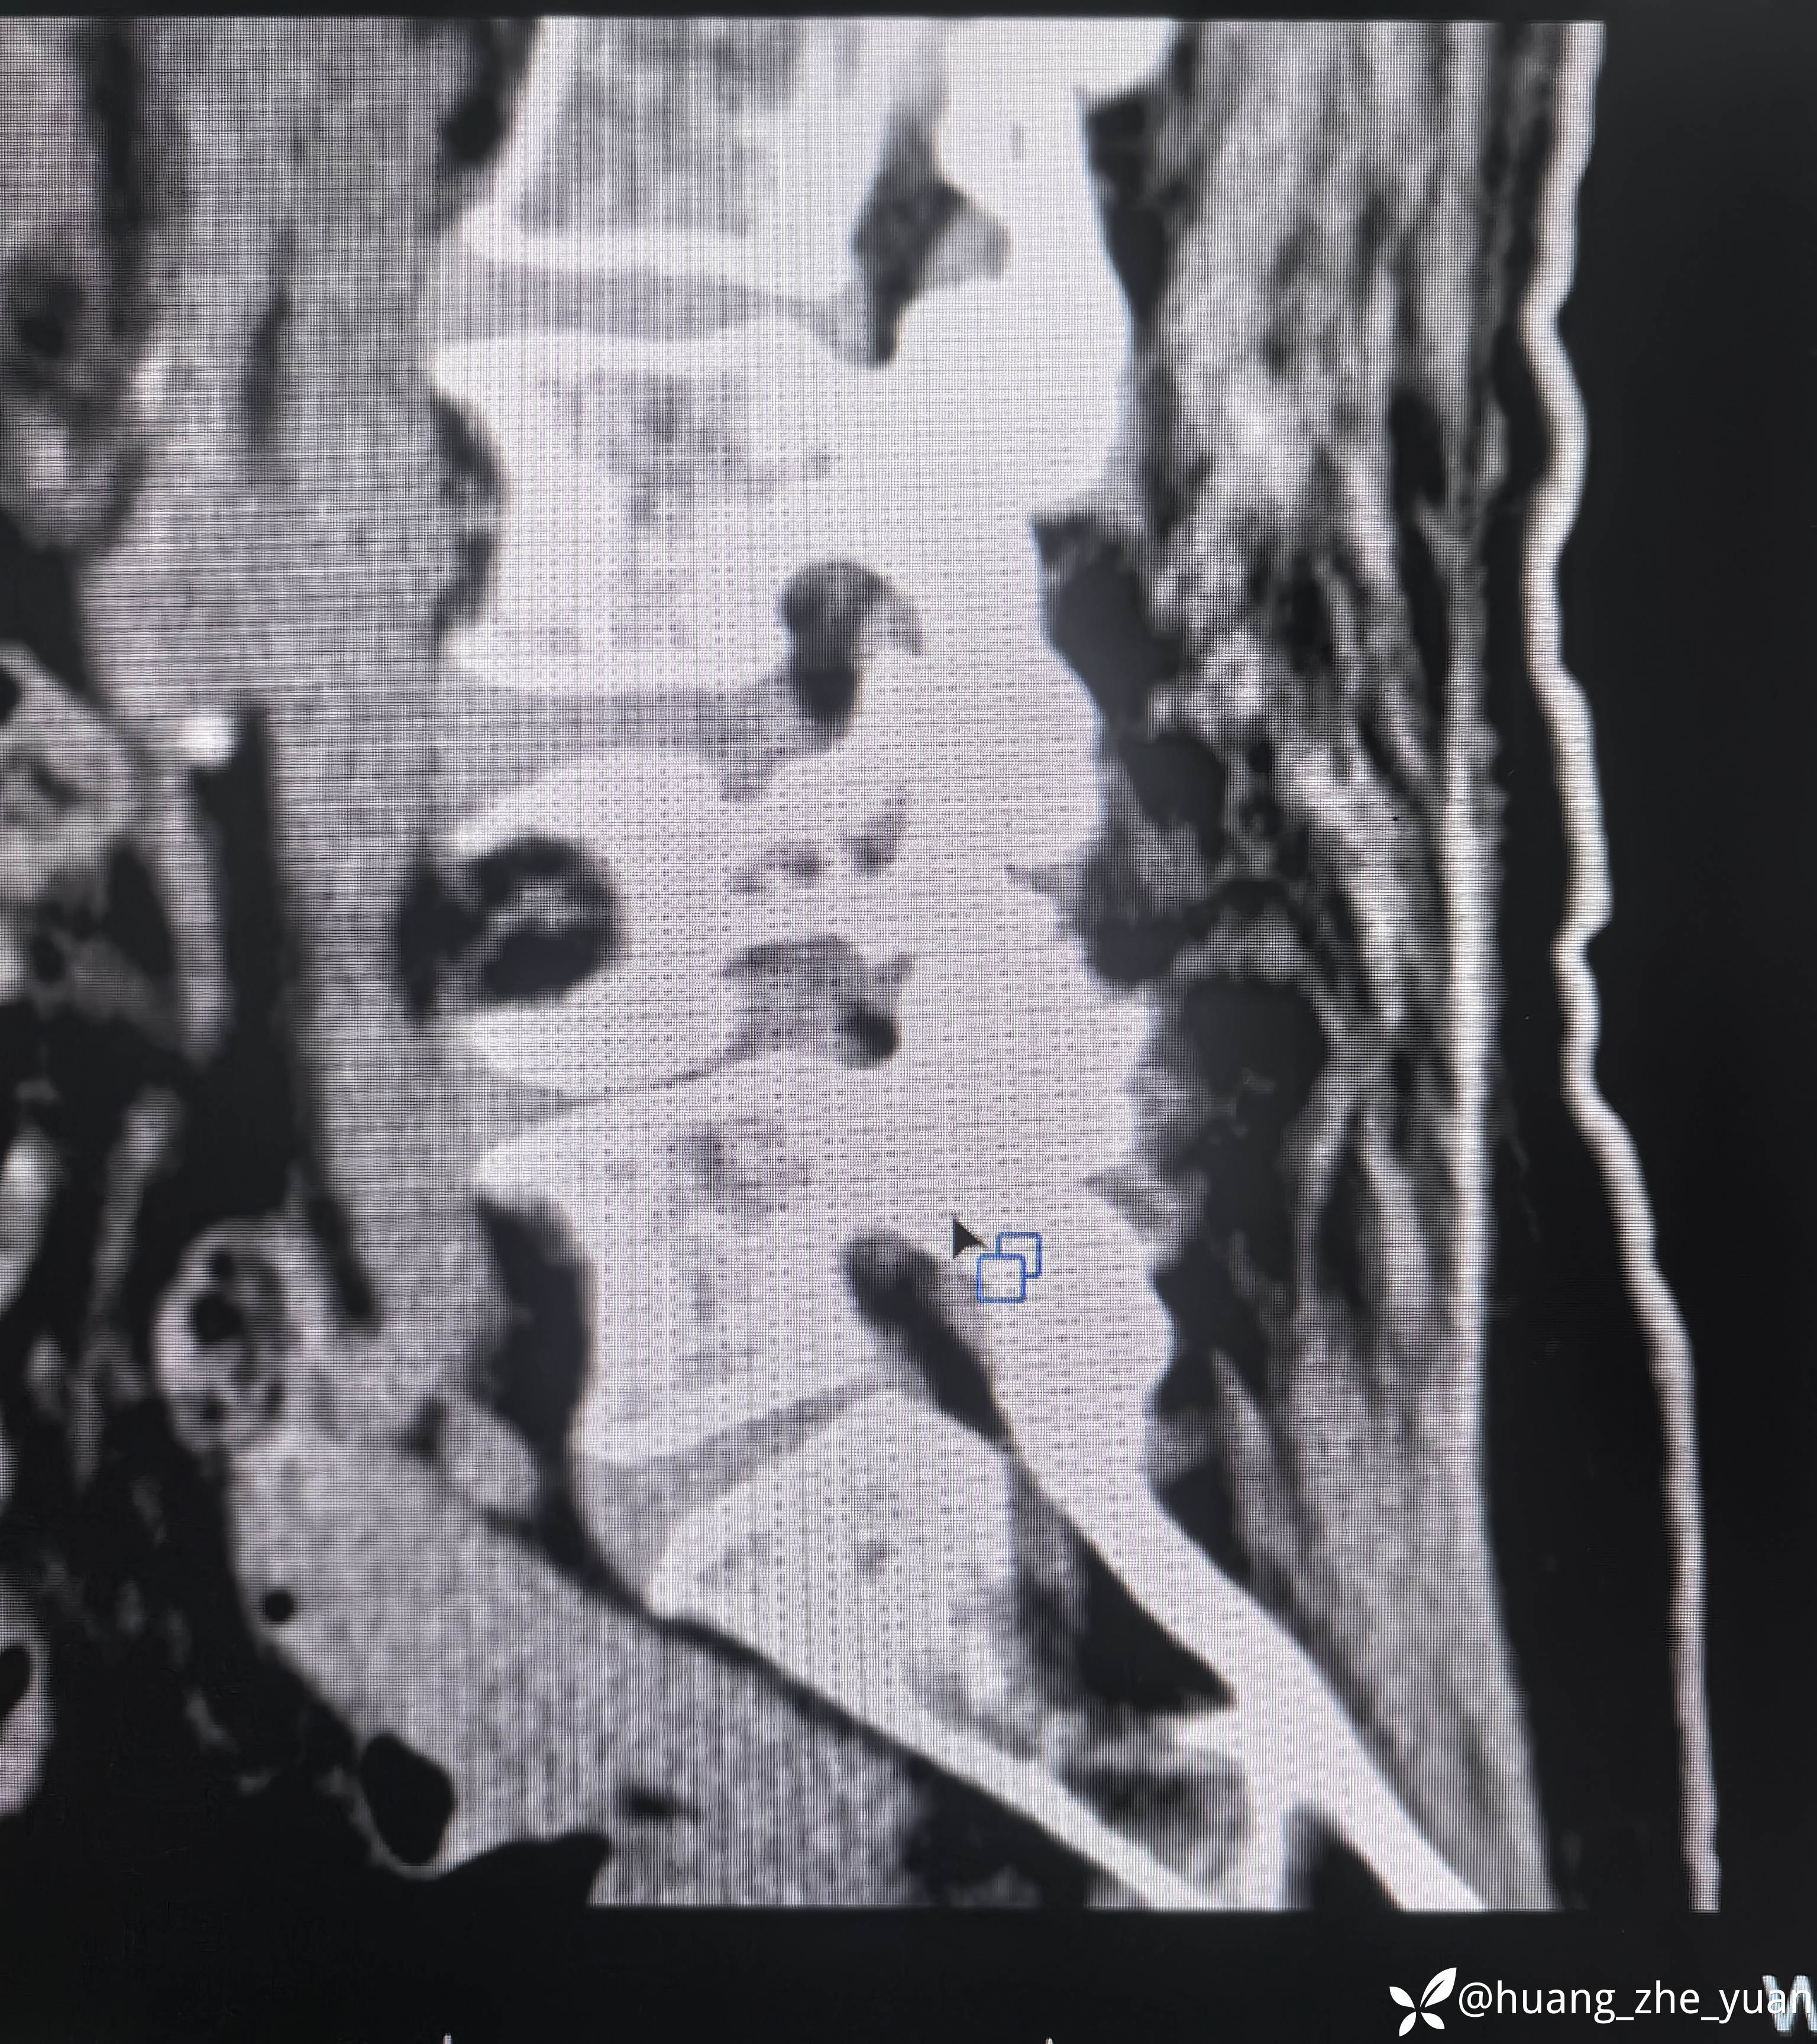

70岁女性,反复右下肢放射痛八个月。合并症:糖尿病,胰岛素泵控制。